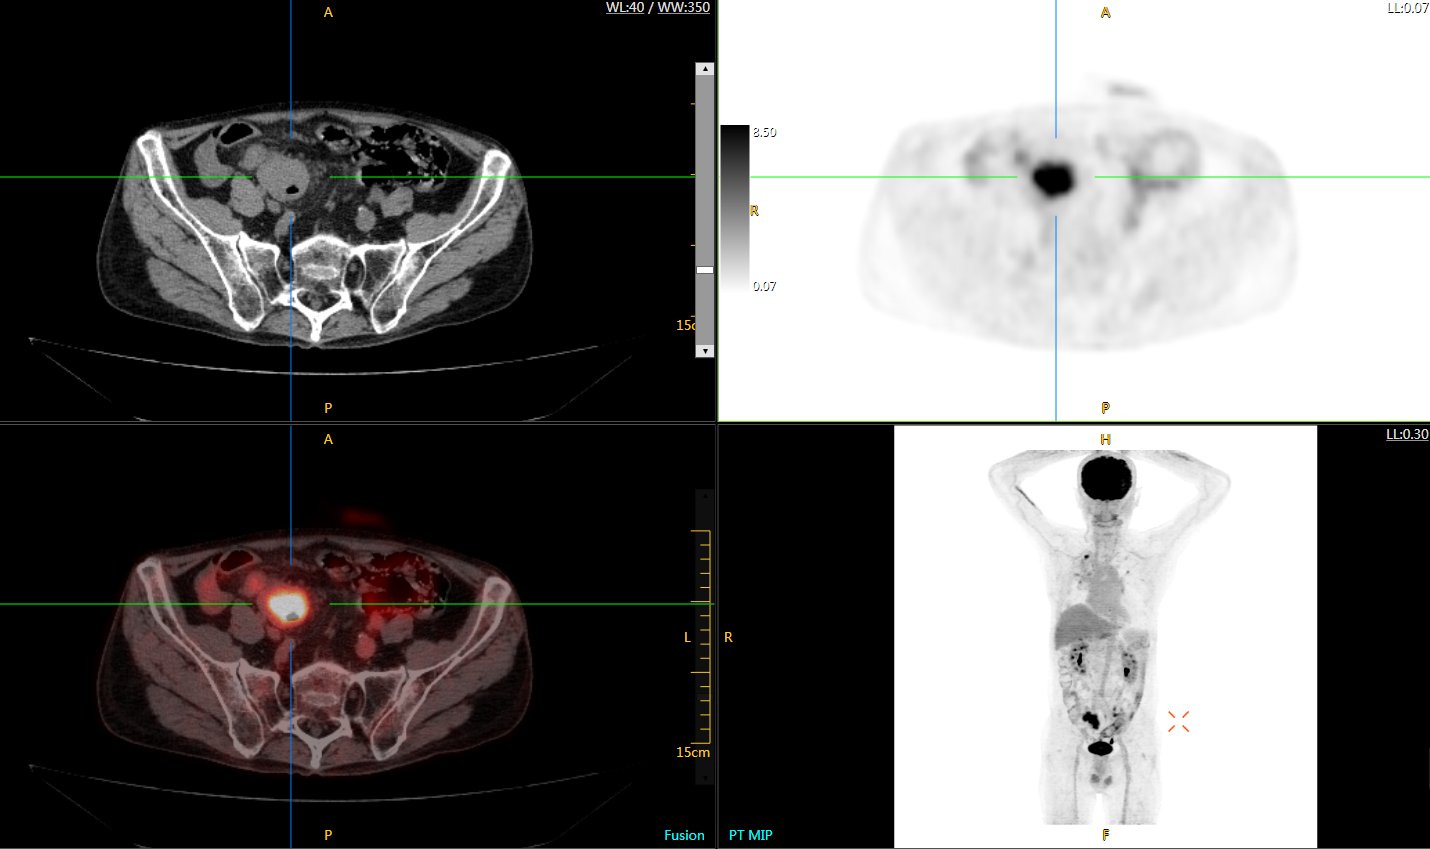

肺癌轉(zhuǎn)移及復(fù)發(fā)

患者男性,66歲,七年前發(fā)現(xiàn)右肺肺癌,其間手術(shù)兩次,共切除兩個肺葉,復(fù)查;

診斷意見,回腸轉(zhuǎn)移,右肺殘留部復(fù)發(fā)